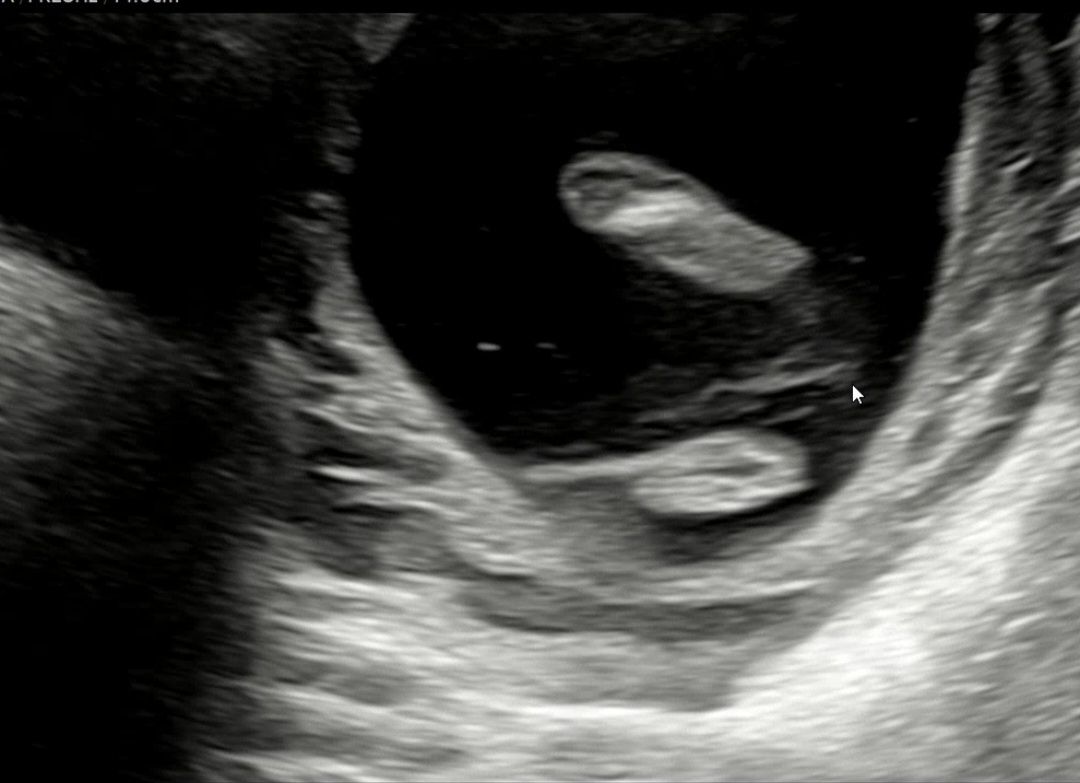

16주 각도법 봐주세요

이건 배로 본 초음파구요. 쌍둥이인데 ㅠ한명은 확실하게 🌶 가 보이는데 다른애는 다리를 계속 웅크려서 애매하네여